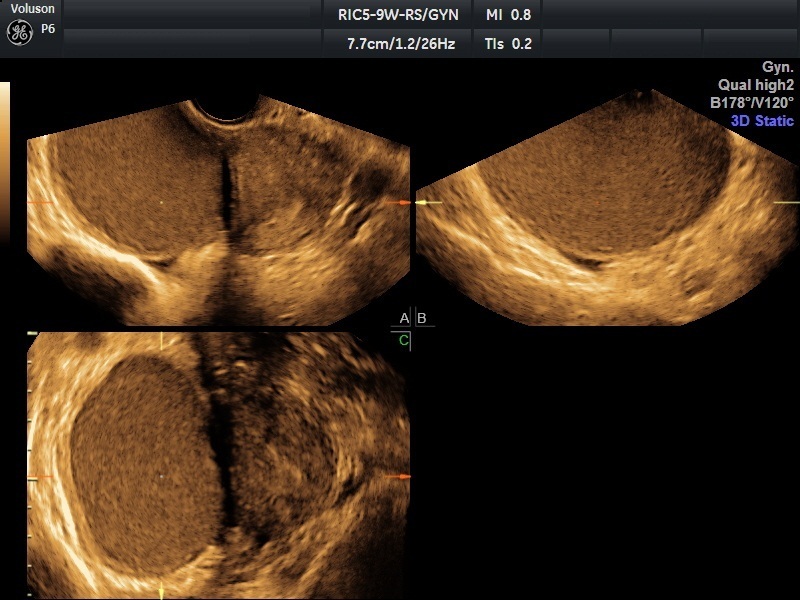

Traditional ultrasounds can miss small or deep infiltrating endometriosis. Advanced gynecological ultrasound, however, combines high-frequency probes, 3D/4D imaging, and specialized Doppler evaluation to provide detailed visualization of the uterus, ovaries, and pelvic structures.

- 3D volumetric scans for a complete anatomical overview